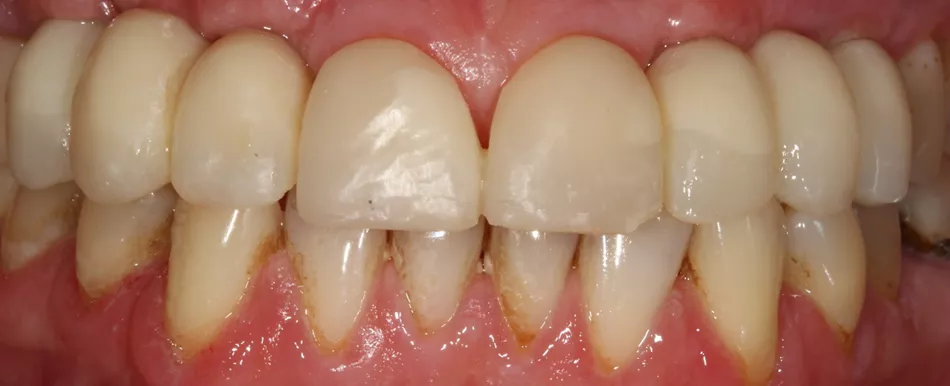

This 65-year-old patient was a non-smoker in good health. He presented with good periodontal status and a low (or maintained low) smile line. Many restorations had been carried out over time, without affecting occlusal function. There was a natural diastema between teeth 11 and 21. There were also two bridges, created to offset agenesis of the maxillary lateral incisors.

1. The two mesially tipped upper canines and first premolars supported two bridges that had been remade 3 times. Repeated decementation in the upper left quadrant and an infection in 2018 made the patient decide to agree to the proposed implant treatment.